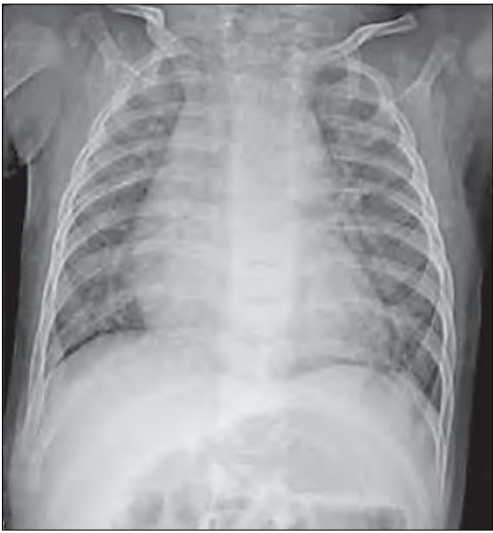

O médico pediatra de plantão é chamado no alojamento conjunto para avaliar um recém-nascido, IG 40 semanas, Apgar 9/10, nasceu há doze horas e está evoluindo com gemência; taquipneia; cianose central; e, queda da saturação de O2. Em ausculta cardíaca, paciente apresenta B2 hiperfonética e única em foco pulmonar. A avaliação radiográfica identifica cardiomegalia e aumento de trama vascular: